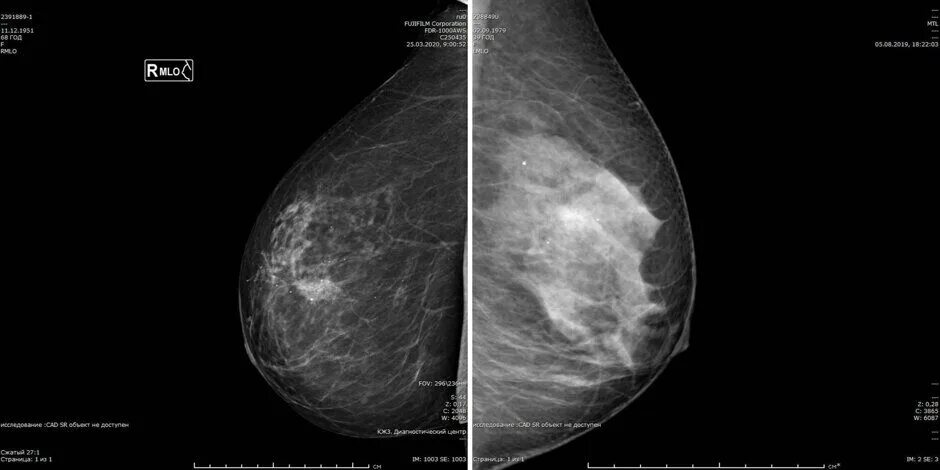

Что значит кальцинат в молочной железе